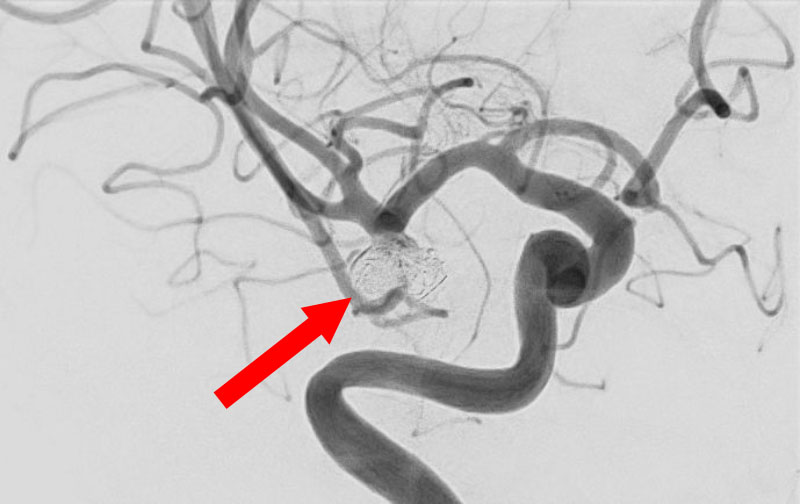

No.1630 手術後